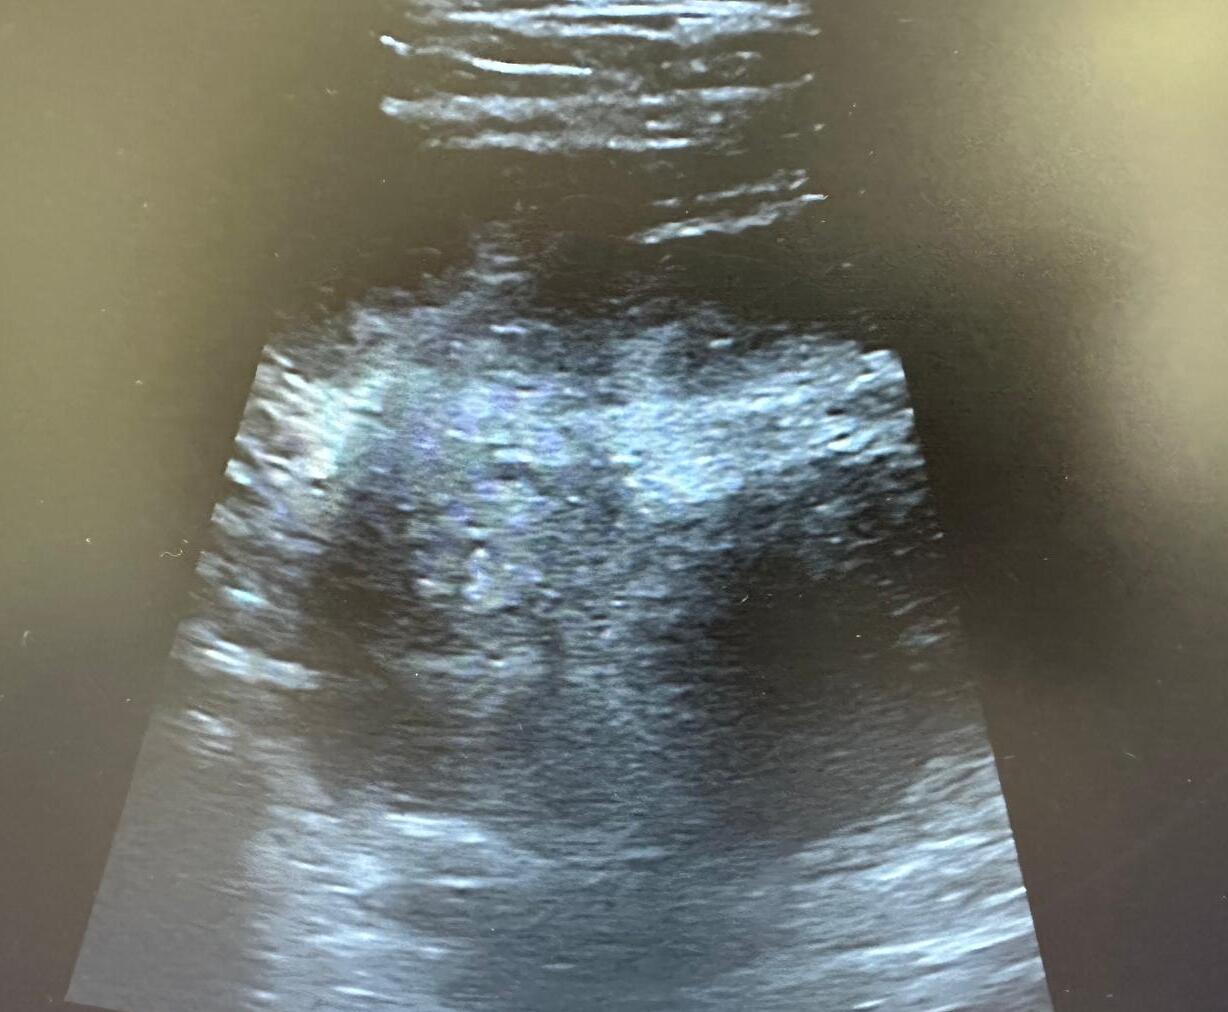

A nivel ecográfico se visualiza imagen profunda, heterogénea, de márgenes poco definidos, sin captación Doppler, más profunda que el margen del glúteo medio.

Con los hallazgos mencionados, se orienta el cuadro como tumoración glútea izquierda con características de malignidad.